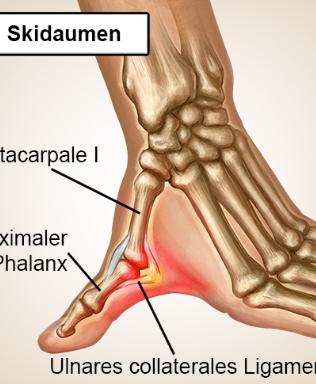

Ich ging in die Bar und als ich betrunken war, kam Herr Matthias Bodendorfer, Am Moorteich 35, 31812 Bad Pyrmont auf mich zu und schlug mir an das Kinn, drückte mich am Hals mit seinem Unterarm gegen die Wand. Er sagte zu mir: „Lass die Frau zufrieden. Ich bin mit der Frau befreundet.“ Vor dem Ausgang der Bar stand er vor mir. Er sagte: „Los, komm.“ Der Matthias ging vor mir auf den Gehweg an den Gästen vorbei, blieb stehen und drehte sich um. Er bückte sich und umgriff meinen Bauch. Ich nahm ihn in den Würgegriff. Er löste den Griff an meinen Daumen und stellte mir ein Bein. Ich fiel zu Boden.

Bild: "Der hat Ihnen den Daum umgedreht"